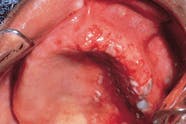

Acute Herpetic Gingivostomatitis

Palatal Cysts of the Newborn

Case 6

Calcifying Odontogenic Cyst

Case 8

Case 9

Case 10

Case 11